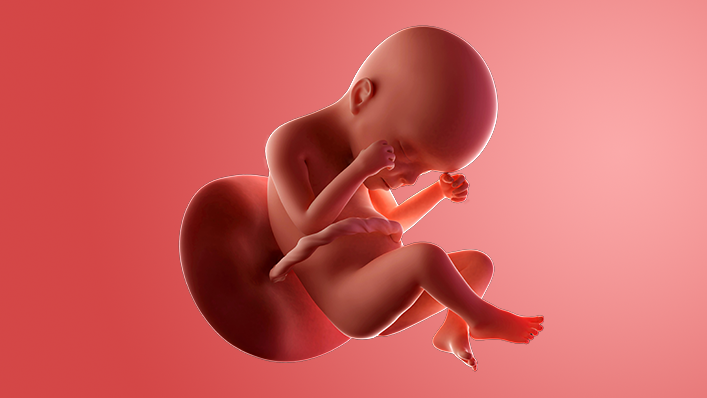

What does my baby look like?

Your baby, or foetus, is around 34.6cm long from head to heel. That's approximately the size of a courgette.

This is an active time for your baby. A loud noise could make your baby jump and kick, which should not hurt but might take you by surprise. You might even feel the occasional hiccup.

Your baby is now peeing into the amniotic fluid. By now, most of the liquid around your baby is urine, which provides cushioning and helps keep the temperature snug and stable.